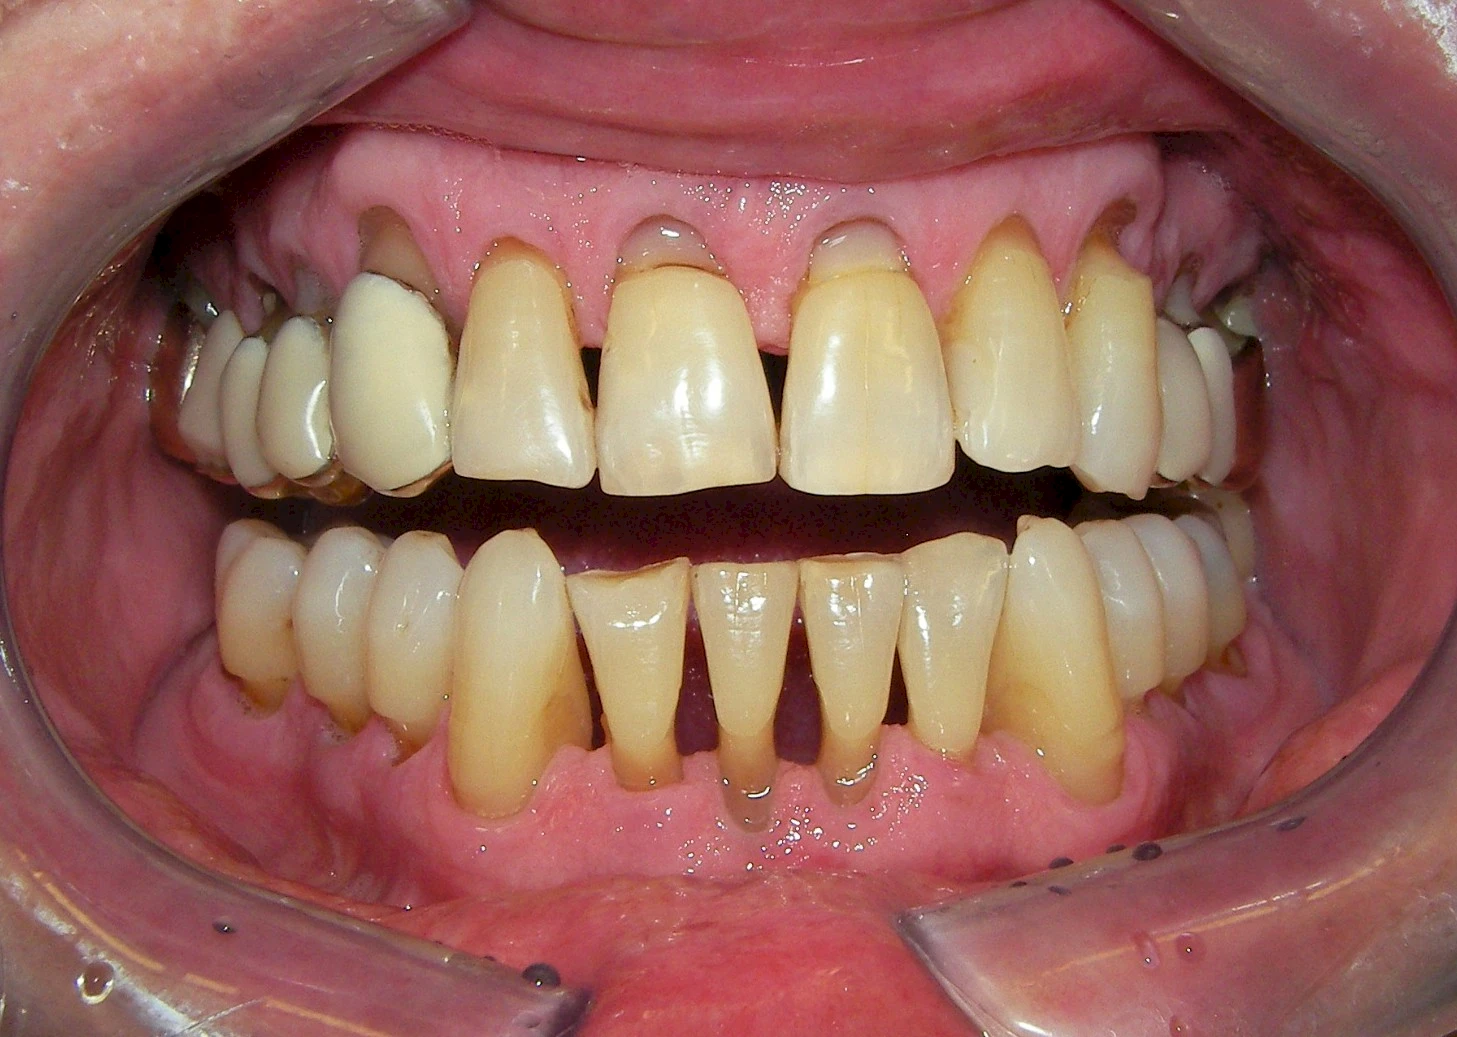

Über die Zeit können verschiedene Prozesse die Zahnhartsubstanzen aufzehren:

- Abnutzung durch Kauen (Abrasion) oder duch durch übermäßiges Knirschen bzw. Pressen (Attrition)

- Säurebedingte Auswaschung (Erosion)

- Knirschen bzw. Pressen und ungünstige Putztechnik (Druck): keilförmige Defekte

Die Zähne können dabei auf Reize (warm, kalt, süß, sauer) oder auch beim Zähneputzen empfindlich oder schmerzhaft sein. In allen diesen Fällen ist es sinnvoll, den Zahnarzt zu kontaktieren und das weitere Vorgehen abzustimmen.